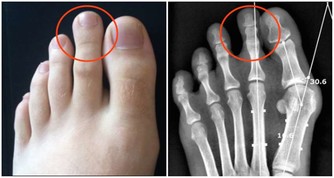

9、 腳踝伸展式:

口令詞:屈雙膝,臀部坐於兩腳跟上,呈金剛坐姿坐好,雙手至體側撐地,吸氣,抬起雙膝離開墊面,雙手攤放在雙膝上,腰背挺直,目視前方。

注意:臀部儘量坐於兩腳心上。感覺困難可將雙手體側撐地。在此維持1-3分鐘。呼氣,雙手體前撐地,雙膝落於墊子上,快速拍打腳背放鬆,抬起雙小腿,輕輕旋轉腳踝放鬆。

功效:有效伸展腳踝,刺激到經過腳踝的四條經絡,胃、脾、肝和膽這四條經絡;靈活踝關節,增強踝關節的承受能力。

10、腳趾蹲式:

口令詞:勾雙腳尖,雙腳趾趾腹觸地,臀部坐於兩腳跟上,雙手攤放在雙膝上,目視前方。

注意:腰背挺直,重心放在腳趾趾上。

功效:有效的加強足部以及腳趾和腳踝的承受力;有效的刺激下半身的6條經絡,擠壓腳踝前側。有助於打開脾經,肝經,膽經,胃經。